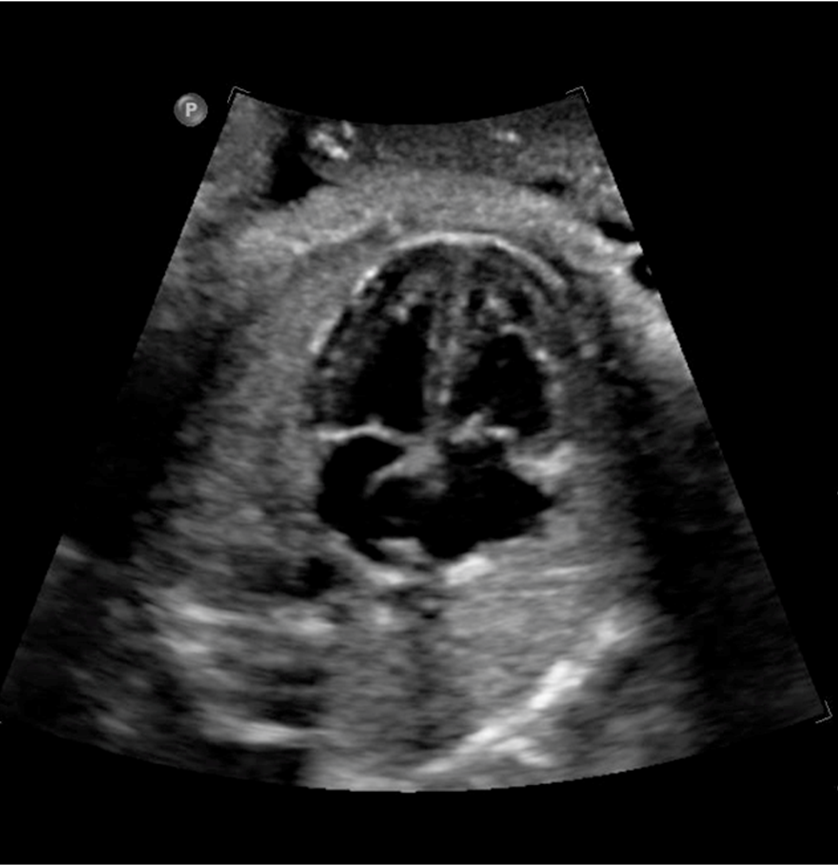

normally what is closest to anterior abdominal wall

right ventricle

what is closest to spine

left atrium

blood flow through foramen ovale

right to left

where is moderator band located

tricuspid valve on ____ side

right

mitral valve on ____ side

left

4 chamber heart should sit at a ___ degree angle and take up about ____ of the chest

45 degree

1/3

___ of the herat located in left chest with apex pointing ____

2/3

checklist for 4 chamber heart

situs

heart position

cardiac size

squeeze ok?

chamber ID and symmetry

septum appearance

AV valve offset

foramen ovale flap

area behind heart

rate and rhytm